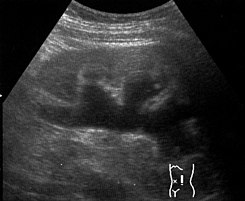

En segundo lugar, nos sirve para evaluar las vías urinarias, uréteres y vejiga, donde podremos ver si existen obstrucciones o dilataciones ureterales (hidronefrosis) o litiasis renal (cálculos). Se puede estimar también la capacidad de la vejiga, y si es que luego de evacuar la orina, hay presencia de un significativo Residuo Post Miccional.

Aunque la sensibilidad para el diagnóstico de cálculos urinarios o litiasis en de solamente el 33% para la ecografía, es un primer estudio a realizar, pues el examen radiológico ideal para diagnosticar la presencia de litiasis, definir el tamaño, la ubicación y composición de la litiasis es mejor la Tomografía sin contraste.